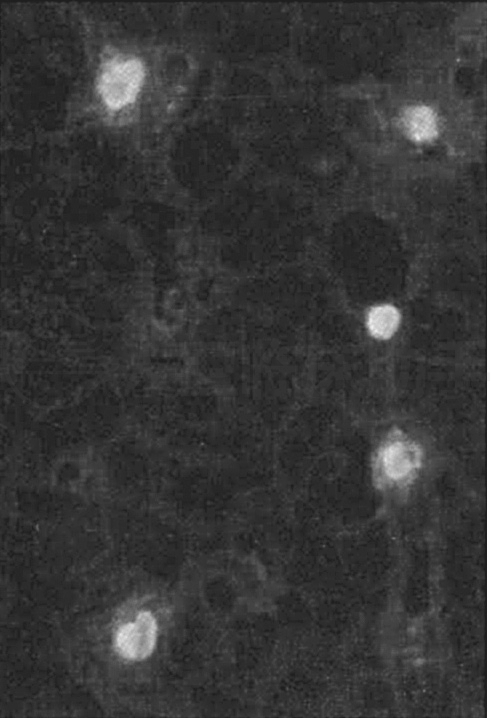

抗中性粒细胞胞浆抗体(antineutrophil cytoplasmic antibodies,ANCA)是一组以人中性粒细胞胞浆各种成分为靶抗原的自身抗体。间接免疫荧光法检测总ANCA是以乙醇或甲醛固定的中性粒细胞置于载玻片上作为抗原,待测血清中的ANCA与之结合后,再加入荧光标记的抗人IgG抗体,在荧光显微镜下,针对不同的靶抗原的胞浆型ANCA(cytoplasm ANCA,cANCA)或核周型ANCA(peripheral ANCA,pANCA),cANCA该型荧光模型表现为均匀分布在整个中性粒细胞胞浆的颗粒荧光,细胞核无荧光(图14-6)。pANCA荧光模型表现为围绕中性粒细胞胞核的带状、平滑的核周荧光,可由多种不同的特异性抗体引起(图14-7)。ELISA法检测特异性ANCA通常采用纯化的特异性中性粒细胞胞浆抗原包被固相反应板,加入受检血清后,待检血清中的特异性ANCA与相应的抗原结合,再加入酶标记抗人IgG抗体,当加入酶反应底物时即出现颜色反应,可检出特异性抗中性粒细胞胞浆抗体。

Fig. 14-6 Positive diagram of cANCA